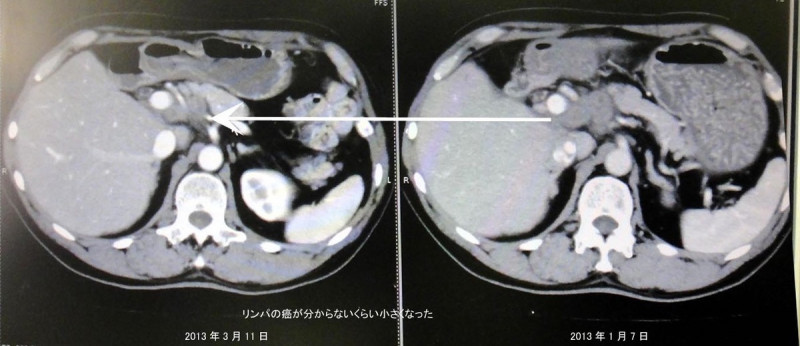

『なんと肝臓の門脈の癌が小さくなるなんて信じられないことが起こったと!!!リンパのガンもわかないぐらい小さくなった』との驚くようなご報告をいただきました。

見た感じではガンが消えているように感じます。ガンが小さくなって正常な細胞に変化してきているようです。病院の先生方も不思議がられています。